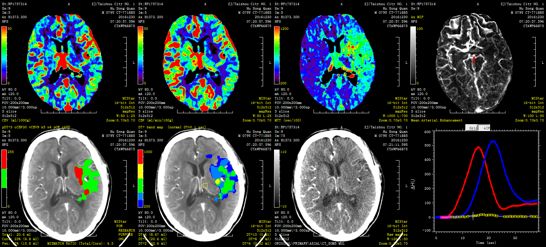

影像表现与评分不符,图像经MIStar处理后,左侧CBV核心区为4ml,半暗带>15ml。

CTA示左侧颈内动脉起始部闭塞,ICA末端显影,大脑中动脉M1闭塞。